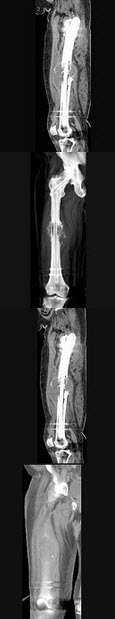

22、单项选择题

男,18岁,右股骨肿瘤术后,出现大腿中段疼痛,夜间尤甚,结合CT图像,最可能的诊断是()

A.骨纤维肉瘤

B.尤文肉瘤

C.骨肉瘤

D.成骨性骨转移瘤

E.化脓性骨髓炎